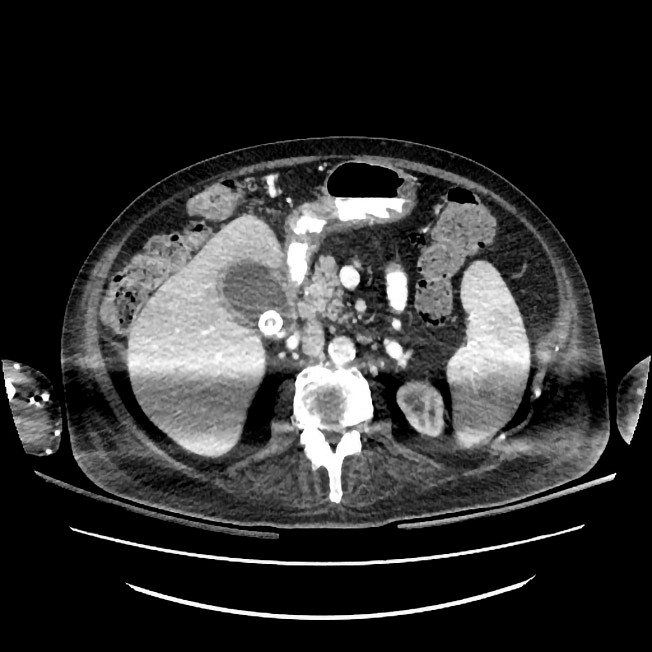

En mann i 70-årene med Bekhterevs sykdom, diabetes type 2 og koronarsykdom ble innlagt på kirurgisk avdeling ved lokalsykehuset etter et fall i en trapp. Ved innkomst til akuttmottak var han bevisst og orientert, men hadde ingen motorisk respons i over- eller underekstremiteter. Det var frie luftveier, regelmessig normofrekvent puls og blodtrykk på 80/60 mm Hg. CT av hodet, nakken, thorax, abdomen og bekkenet etter traumeprotokoll viste en columnafraktur i nivå C4–C5. Etter CT-undersøkelsen ble pasienten ukontaktbar. Blodgassmåling viste respiratorisk acidose, og det var mistanke om hypoventilasjon. Pasienten ble umiddelbart intubert. Supplerende CT caput med angiografi viste ingen tegn til traumatisk blødning, men derimot opphørt sirkulasjon i begge vertebralisarterier med retrograd fylning av bakre cerebrale kretsløp, forenlig med dislokasjon av vertebralisarteriene som følge av columnafraktur. Mannen ble overflyttet til nevrokirurgisk avdeling ved nærmeste regionsykehus og operert på vital indikasjon med reposisjon av cervikal fraktur og osteosyntese. MR av hjernen etter operasjon viste gjenopprettet sirkulasjon i vertebralisarteriene uten gjennomgåtte hjerneinfarkter. MR av ryggmargen viste ryggmargsødem i nivå C2–C5, forenlig med ryggmargsskade (figur 1).